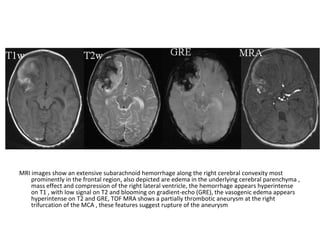

Cerebral venous thrombosis in a 44 year old woman, axial (a) and sagittal (b) T1

show high signal intensity in the deep cerebral veins (arrow) and venous

sinuses (arrowheads), (c) 3D MIP from MR venography demonstrates

collateral vessels (arrowhead) secondary to occlusion of the cortical veins and

venous sinuses (arrow)